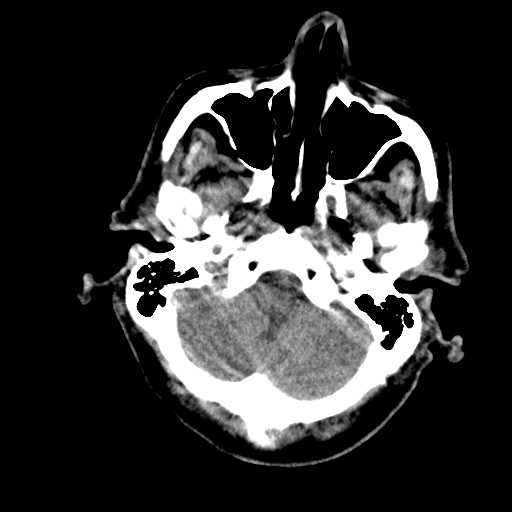

Figure 1: Illustrative examples of different types of brain hemorrhages in CT scans. The hemorrhagic regions are highlighted in red. (a) IPH, (b) IVH, (c) EDH, (d) SAH, (e) SDH.

The dataset used in this study was collected from two medical centers in Tehran, Iran: Rasoul Akram Hospital and Firouzabadi Hospital, over a period spanning 2018 to 2024. All CT scans were manually labeled hierarchically by two board-certified neurosurgeons to ensure accurate classification of ICH subtypes. The labeling process involved an initial annotation by one neurosurgeon, followed by validation and verification by a second expert to minimize errors and inconsistencies. Fig. 1 illustrates representative examples of different ICH subtypes in brain CT scans. The hemorrhagic regions are highlighted in red for better visualization. These annotated examples provide insight into the distinct imaging characteristics of each hemorrhage type, emphasizing the variability in their locations and appearances within the brain. The study received ethical approval, and data collection was conducted in compliance with institutional review board (IRB) regulations and the Declaration of Helsinki, ensuring patient confidentiality and adherence to ethical standards.